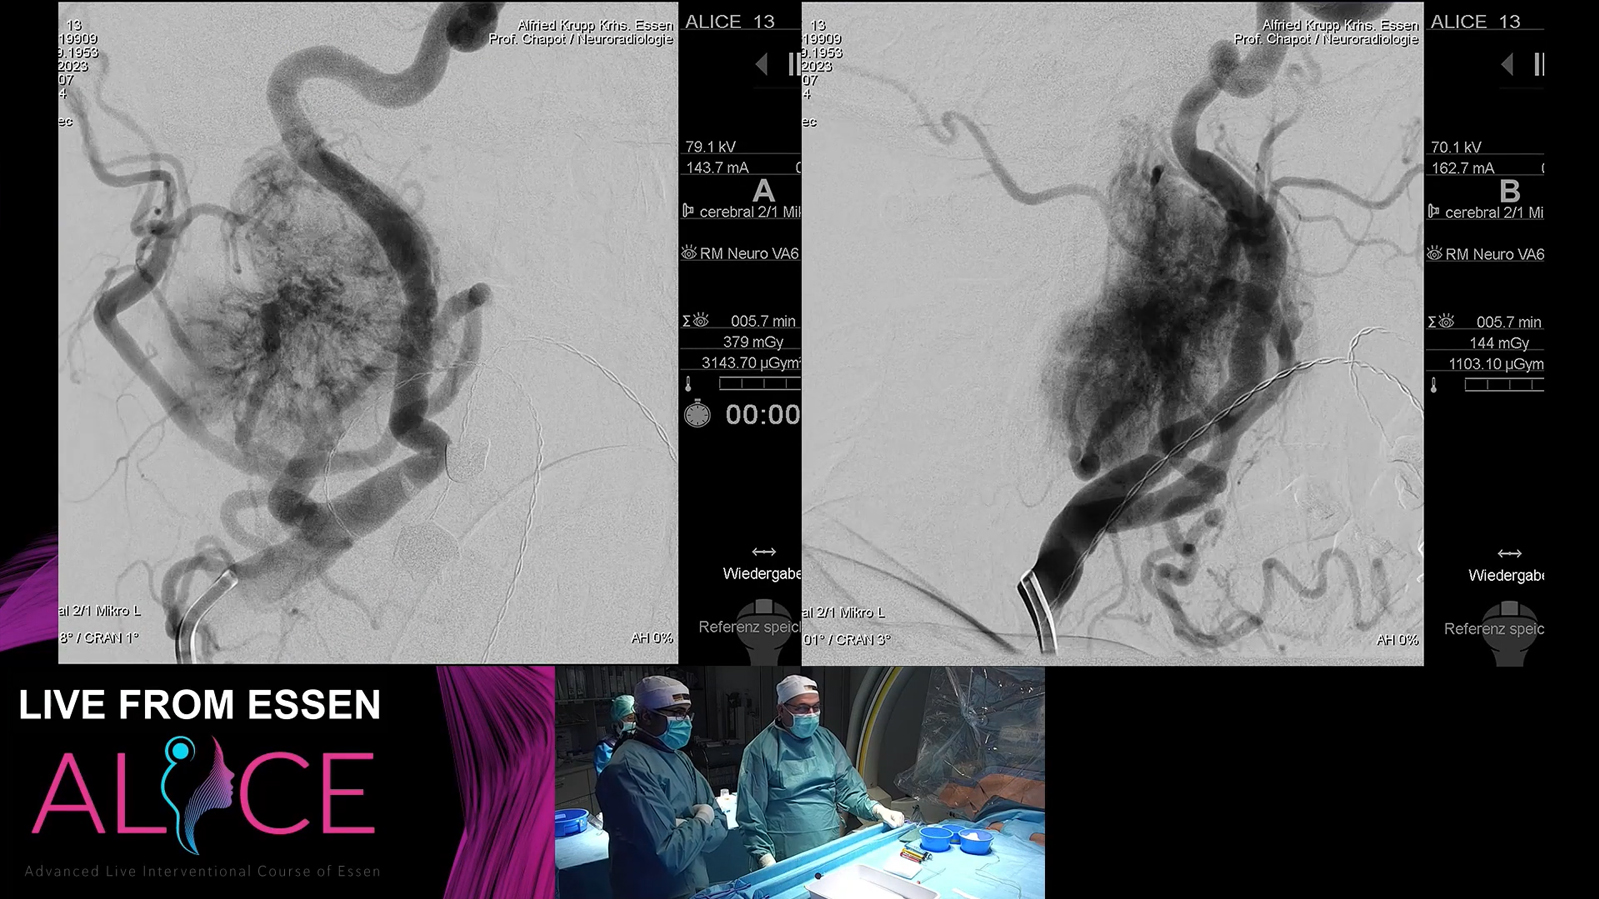

from Essen: AVM treated by TVE